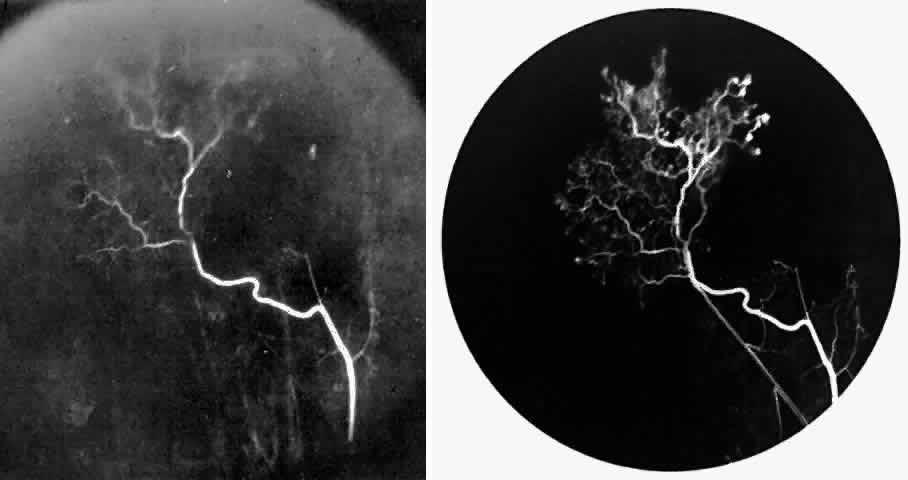

STAGE II: PERIPHERAL ARTERIOLAR-VENULAR ANASTOMOSES. Following occlusion of the terminal arterioles, anastomotic channels form to channel the blood from the occluded arteriole to the nearest venules. These anastomoses form at the interface between the perfused and nonperfused retina. Most likely, they are dilated preexisting capillaries rather than new vessels, since they do not leak on fluorescein angiography. The redirection of blood flow is probably due to hydrostatic forces (Figs. 22 and 23).

Fig. 22. A. Photograph of the peripheral retina, demonstrating capillary occlusions and exudate at the margin of perfused retina. B. Fluorescein angiogram of irregular capillary border, with capillary stumps extending into nonperfused retina and an arteriolar-venular anastomosis demonstrating stage II retinopathy.

Fig. 23. Fluorescein angiogram of continuous arteriolar-venular anastomosis demonstrating stage II retinopathy. (Note that this is the same eye demonstrating the qualitatively abnormal peripheral capillary border in Figure 25.)